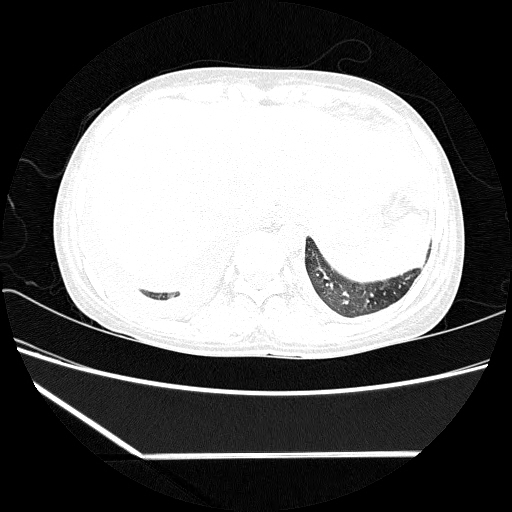

(HRCT)CT-Scan investigation done on 19Aug15 :

Series4